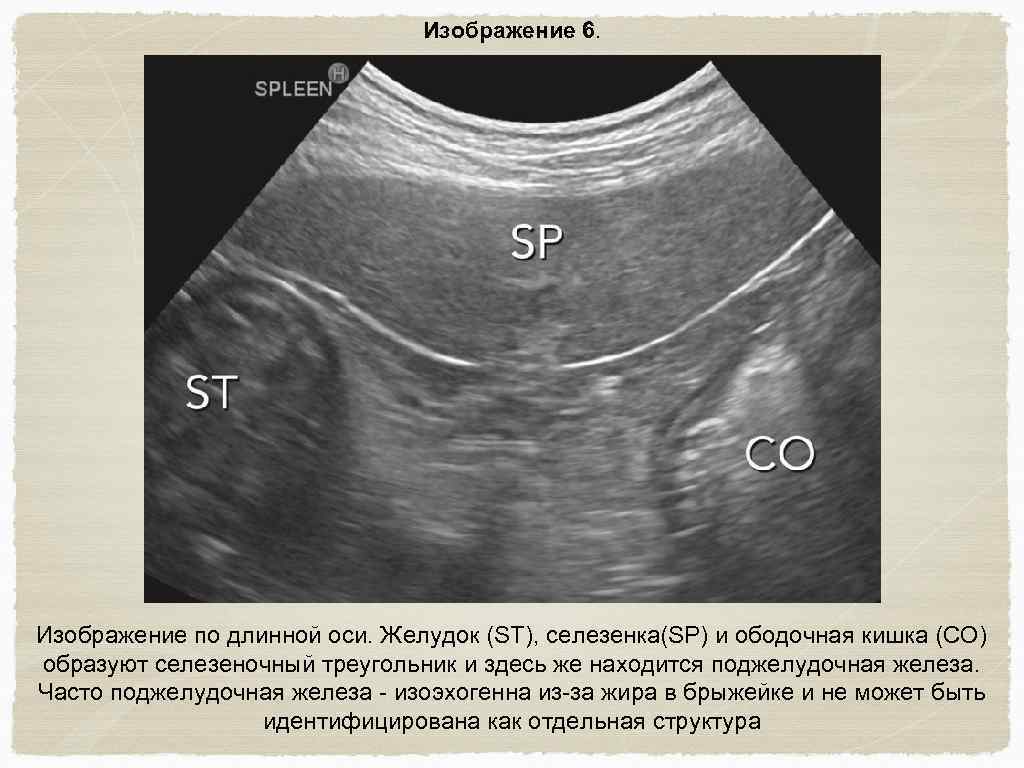

Желудочно-кишечный тракт и поджелудочная железа Исследование проводится в среднем отделе брюшной полости ; установите датчик по длинной оси каудально к печени, так чтобы была видна поперечная проекция желудка. Сдвиньте датчик каудально для определения ободочной кишки в поперечной плоскости (изображение 6) Левая доля поджелудочной железы расположена между желудком и ободочной кишкой, прилегает к селезеночной вене, которая пересекает брюшную полость слева на право и формирует воротную вену. (изображение 7) Вращайте датчик в поперечной плоскости и двигайте его вдоль правой стороны желудка в пилоро-дуоденальное соединение. (изображение 8) Вместе с датчиком, лежащим в поперечной плоскости (с пометкой правой стороны пациента) , следуйте дистально двенадцатиперстной кишки

Изображение 6. Изображение по длинной оси. Желудок (ST), селезенка(SP) и ободочная кишка (CO) образуют селезеночный треугольник и здесь же находится поджелудочная железа. Часто поджелудочная железа - изоэхогенна из-за жира в брыжейке и не может быть идентифицирована как отдельная структура